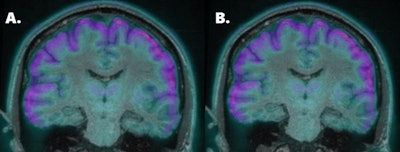

The researchers simultaneously acquired PET/MRI scans (Biograph mMR, Siemens Healthineers) from 15 patients with medically refractory epilepsy immediately after a clinical PET/CT scan. Patients received approximately 185 MBq of FDG prior to 30 minutes of image acquisition for PET/MRI and PET/CT 40 minutes after injection. PET/MRI data were corrected for attenuation using CT and the Resolute MR attenuation correction method.

PET images were reviewed and rated visually for metabolic activity in the frontal, temporal, parietal, and occipital lobes and cerebellum. The patients' PET scans were compared with results from healthy control subjects. The researchers also calculated the mean relative difference between the two PET images for the whole brain and for selected regions.

The researchers discovered a strong correlation between PET attenuation correction methods across brain regions (p < 0.0001), particularly in the mesial temporal lobe (p < 0.0001), which is associated with medically refractory epilepsy. Visual assessments between PET/MRI and clinical PET/CT matched in all but three patients. In that trio, PET/MRI revealed mild abnormalities not reported on PET/CT.